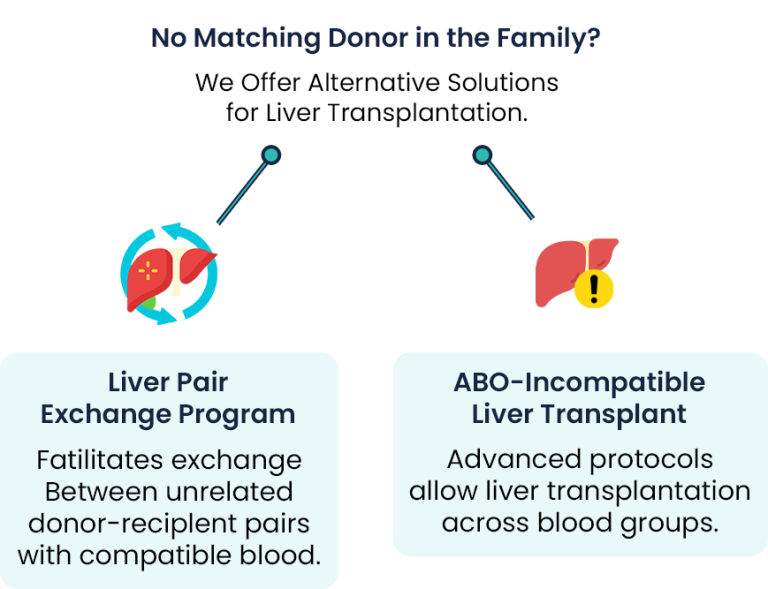

Explore Alternate Liver Donation Options